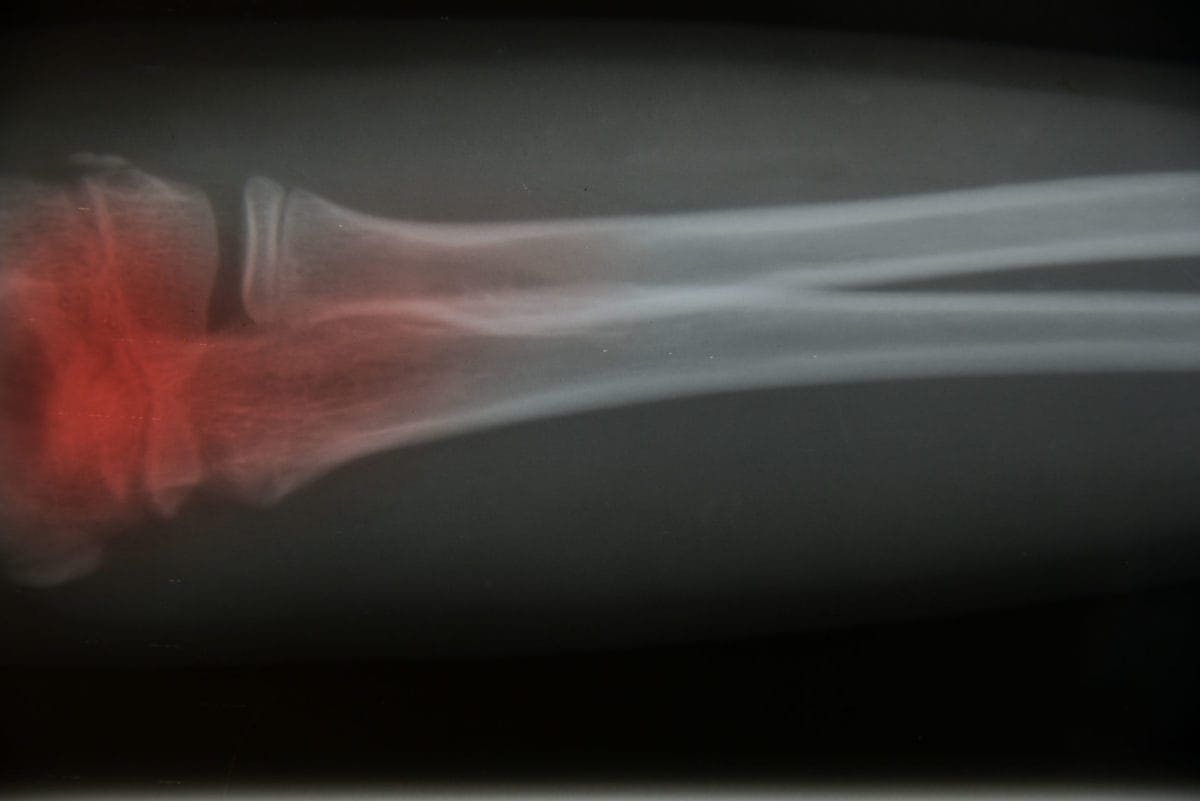

Bone Cancer | Symptoms and Treatment

Bone cancer is a rare but serious condition that starts in the cells of your bones. Knowing the common bone cancer symptoms and treatment options can help you recognize warning signs early and get the right care. With early diagnosis and a personalized treatment plan, many people can manage the condition and improve their quality of life.

There are several tests your doctor may do to look for and diagnose bone cancer. If the doctor finds a tumor, they will need to find out if it is cancerous or not. These tests may include:

• X-rays